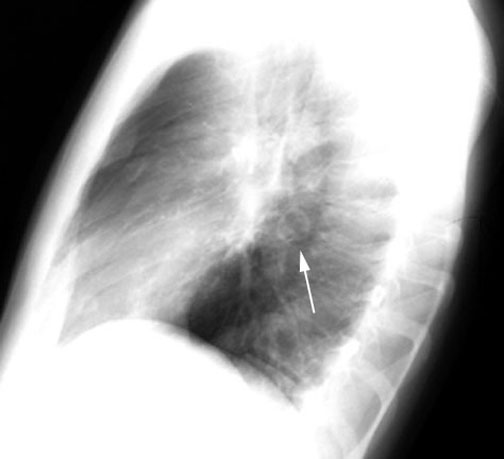

Coccidioidomycosis

Thin walled cavity